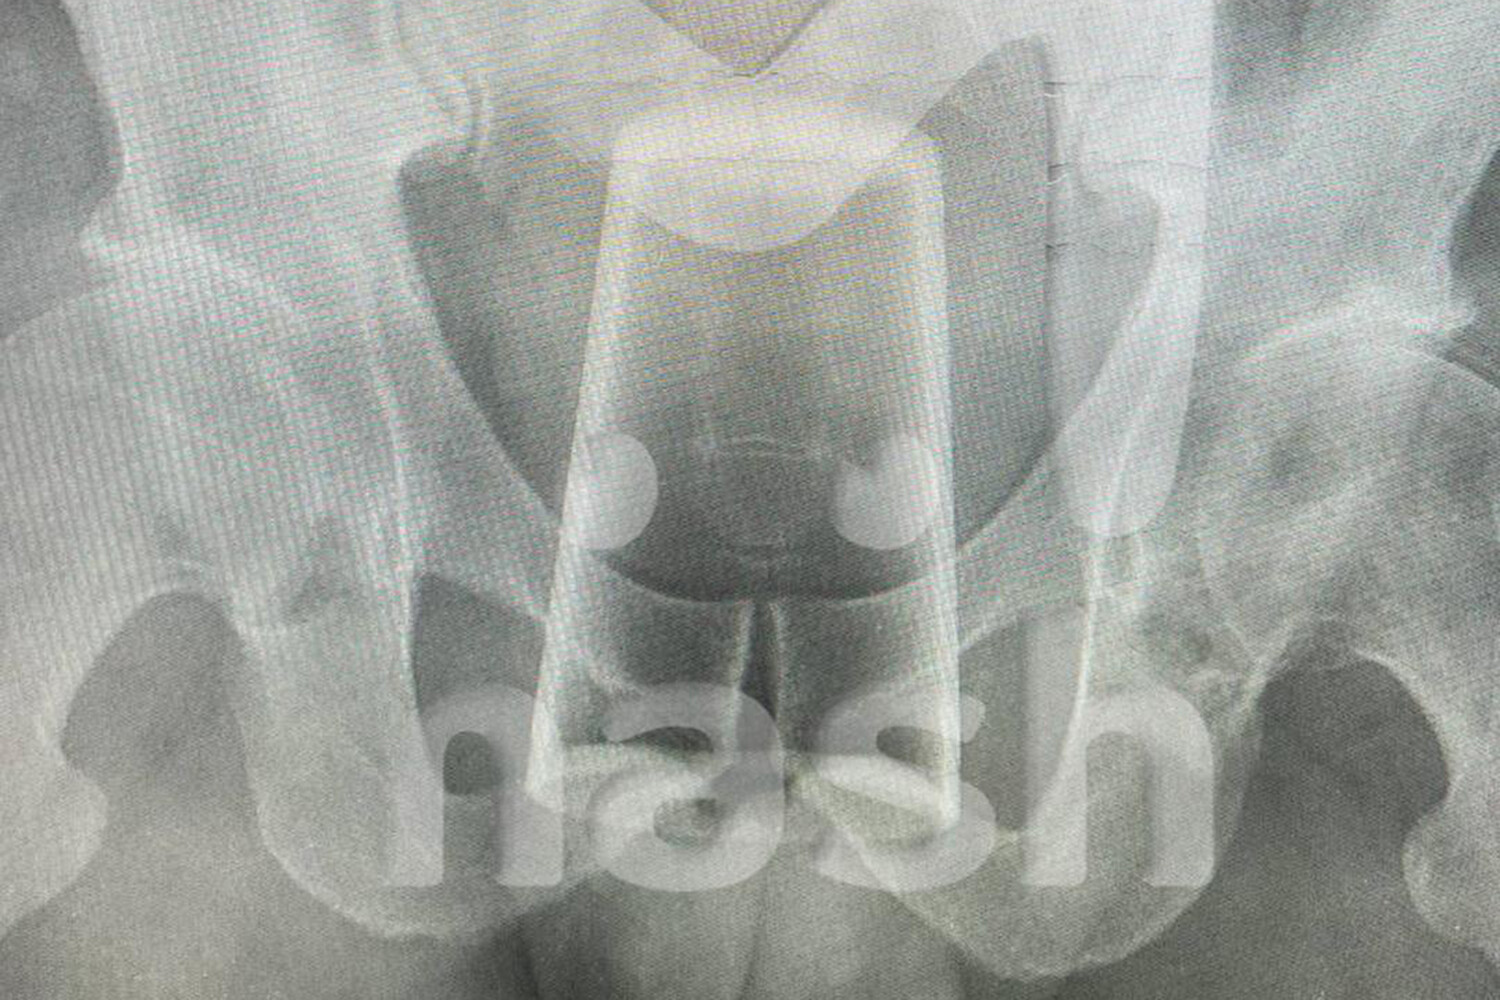

Уфимец обнаружил стакан в заднем проходе после конкурса на 23 февраля

Mash: конкурс на 23 февраля обернулся для уфимца стаканом в заднем проходе

В Уфе мужчина попал в больницу со стаканом в заднем проходе после конкурса на 23 февраля. Об этом сообщает Telegram-канал Mash.

Инцидент произошел в День защитника Отечества, когда двое друзей отмечали праздник. По словам пострадавшего, они с товарищем выпили, закусили и решили устроить конкурс. Однако в какой-то момент он поскользнулся и нечаянно упал на стакан, после чего тот оказался у него в заднем проходе.

Попытки самостоятельно вытащить инородное тело не увенчались успехом — пострадавшему вызвали медиков. Позже врачи извлекли стакан из заднего прохода мужчины и отпустили его домой, порекомендовав регулярно наблюдаться у специалистов после случившегося.